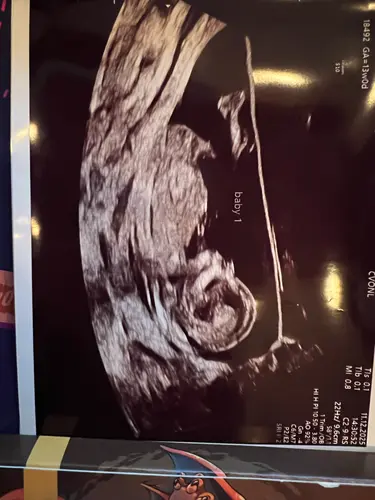

Wat denken jullie bij deze hahah

Heb je geen nub foto? zij foto

Deze heb ik

Hoeveel weken ben je hier precies? Er staat 11w in je profiel

Ja 11 weken en 3 dagen

Ohh veeeel te vroeg. Tis nu een meisje maar het kan zéker nog jongetje worden als ik naar de foto's kijk. Dus volgende echo weer ff plaatsen dan is het vast duidelijk en met (meer) zekerheid te zeggen.